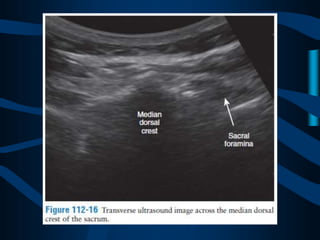

ABORDAJE

TRANSCOCCIGEO